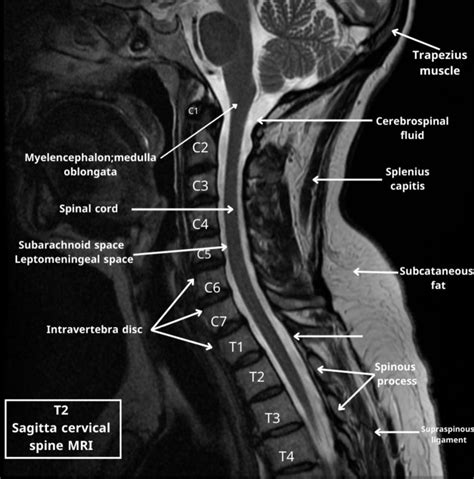

• Neurology: Used for diagnosing conditions such as brain tumors, stroke, and neurodegenerative diseases.